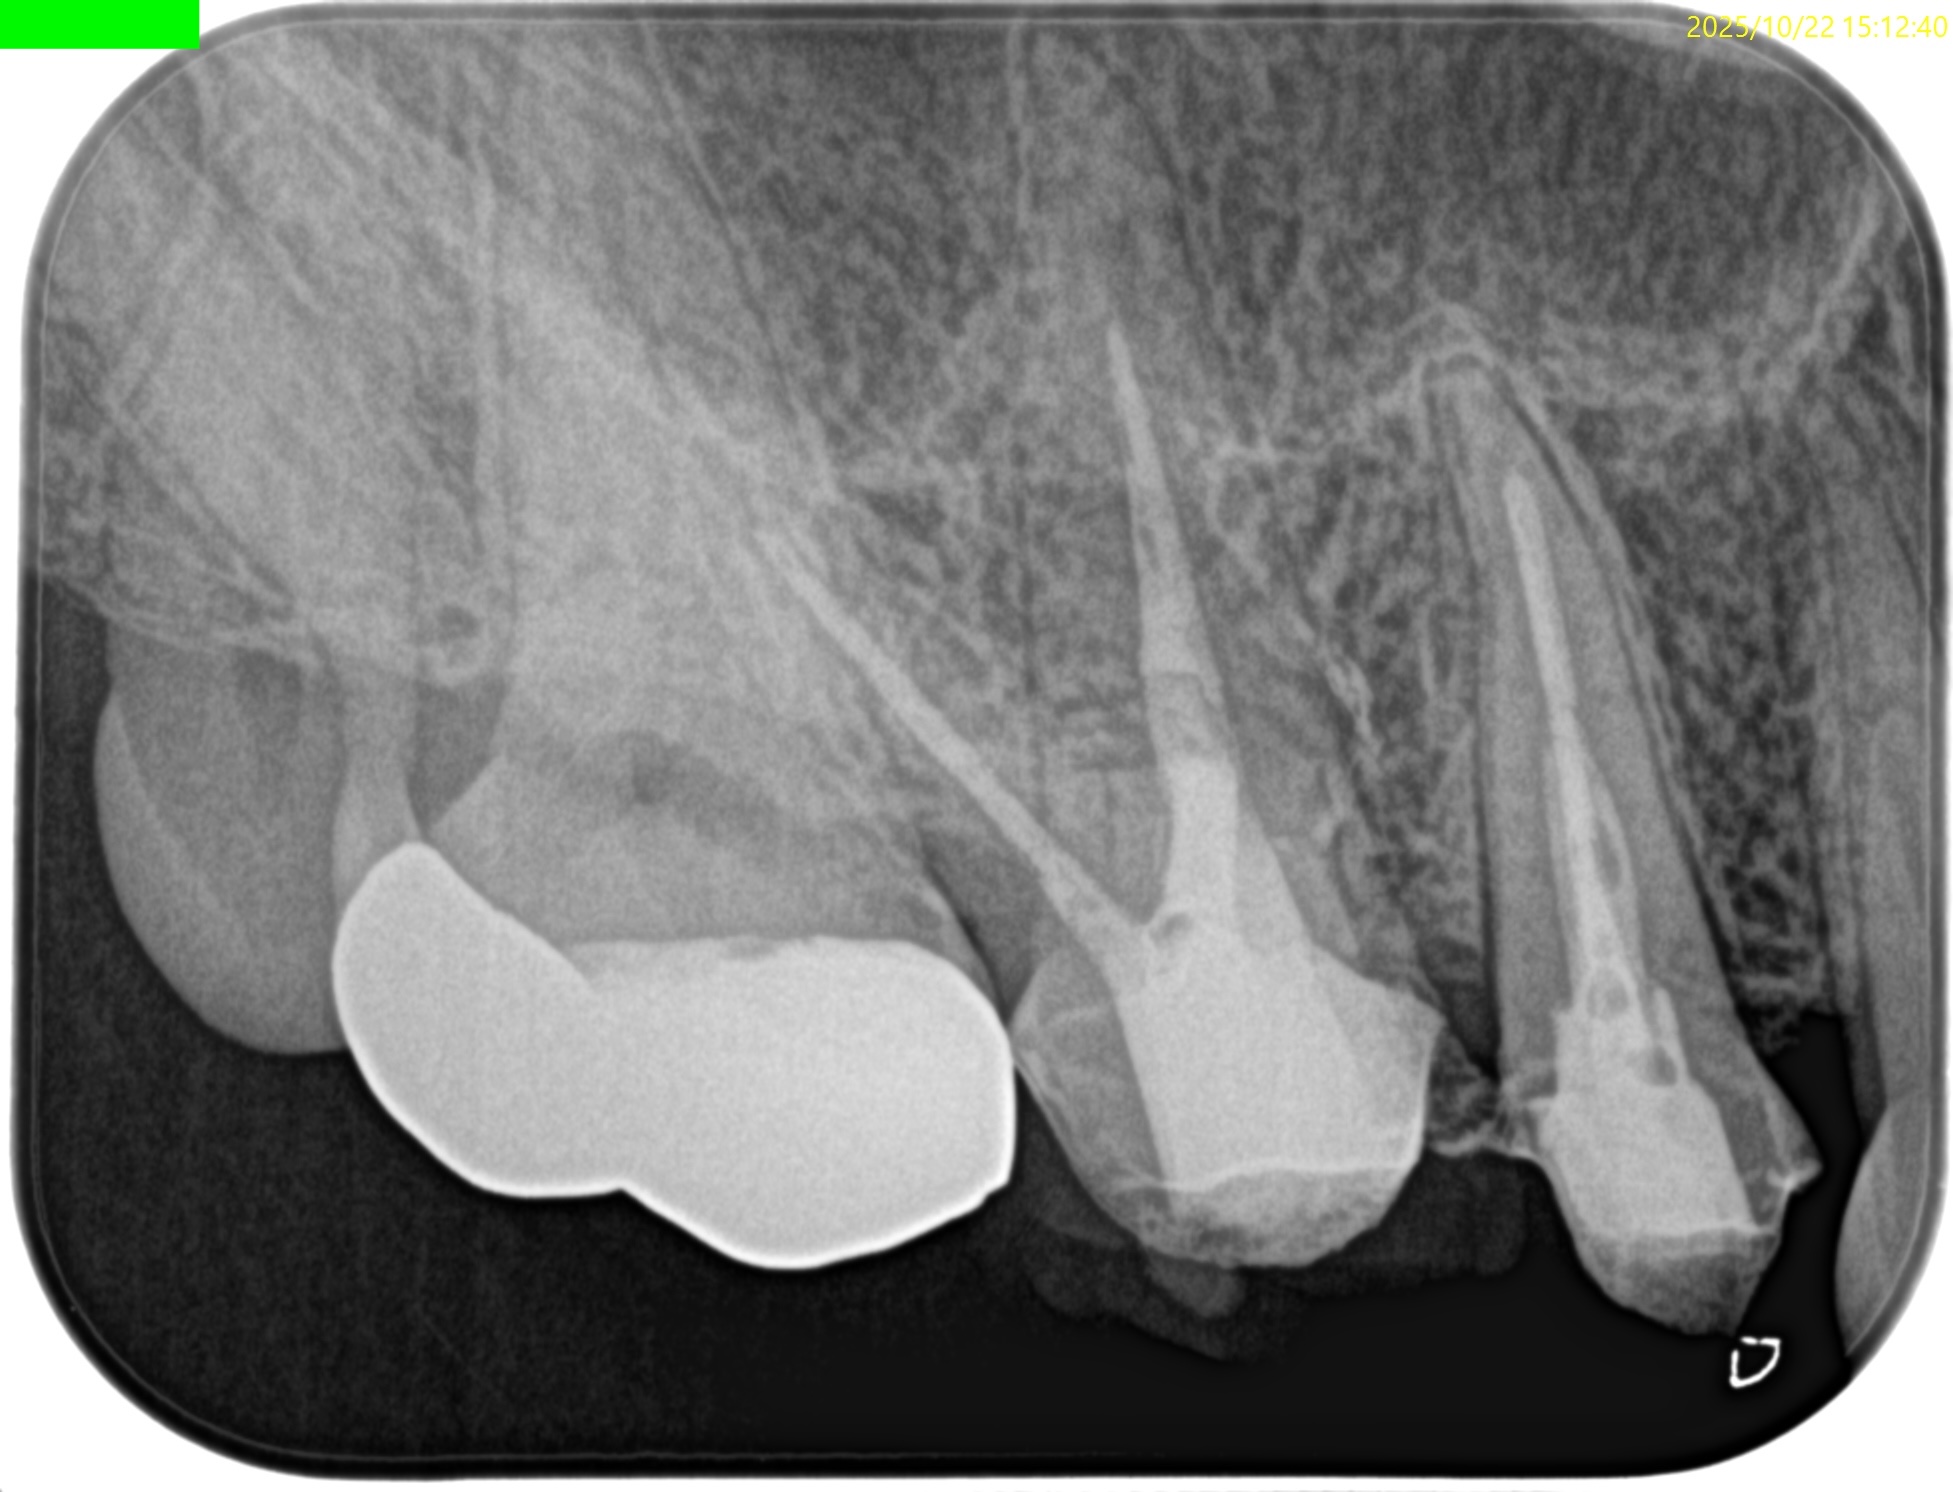

#3 MB Apicoectomy(2025.10.22)

CEJよりも10mm下方の#3 MBのApexをOsteotomyで探索する。

このApexから4mmの部分を想定しRoot resectionした。

今回は折れたFileごとMBのApexを除去した形だ。

この後メチレンブルーで染めて逆根管形成した。

逆根管充填した。

術後にPA, CBCTを撮影した。

問題はないだろう。